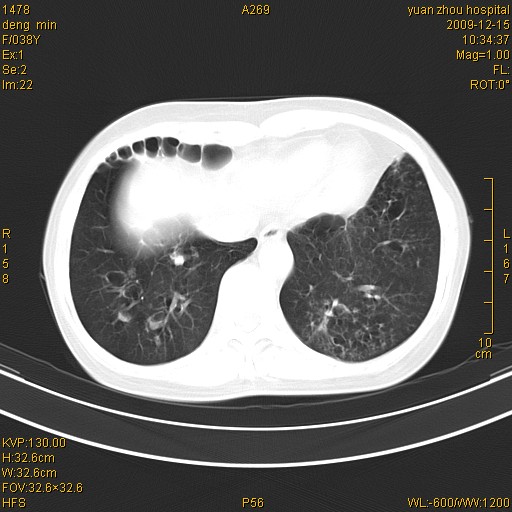

标题: CT23919:F38Y 咳嗽月余 [打印本页]

标题: CT23919:F38Y 咳嗽月余

支气管扩张。典型。

右肺中下叶、左肺上叶舌段及左肺下叶支气管扩张合并感染。